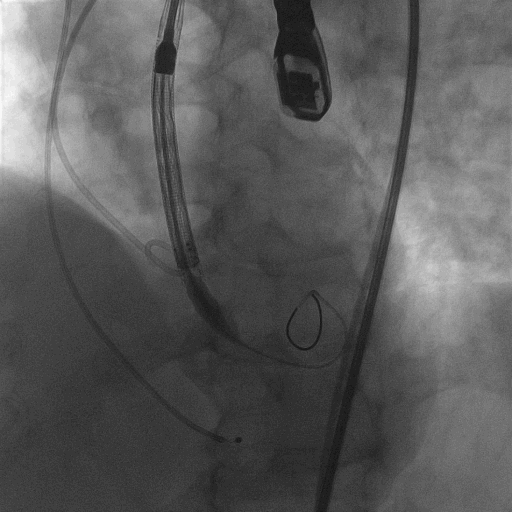

术中造影

18mm球囊预扩,有腰无漏

L23超高位释放

释放到2/3,观察瓣膜位置,与FEops评估一致,瓣膜发生了下滑

使用VenusA-Plus®回收功能以后,调整投射角度继续以高位释放

再次释放到2/3,造影观察瓣膜位置良好,选择全部释放

L23高位释放成功